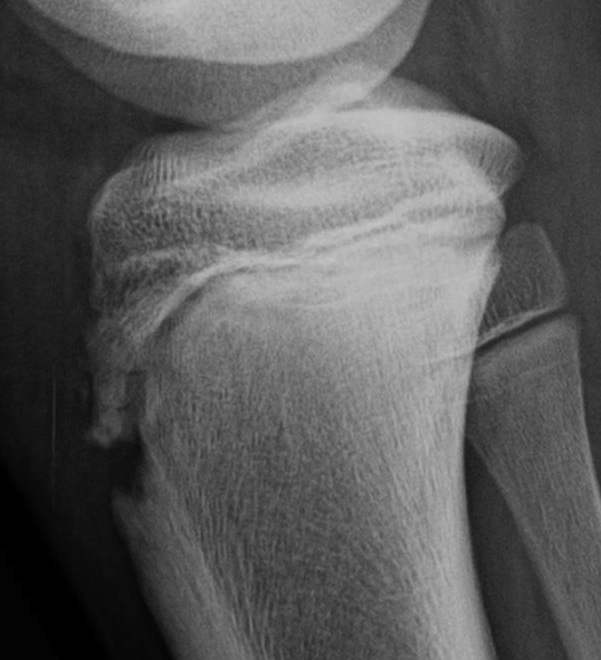

CT / MRI scan

CT scan - ensure fracture doesn't involve the physis / disrupt articular surface

Type III